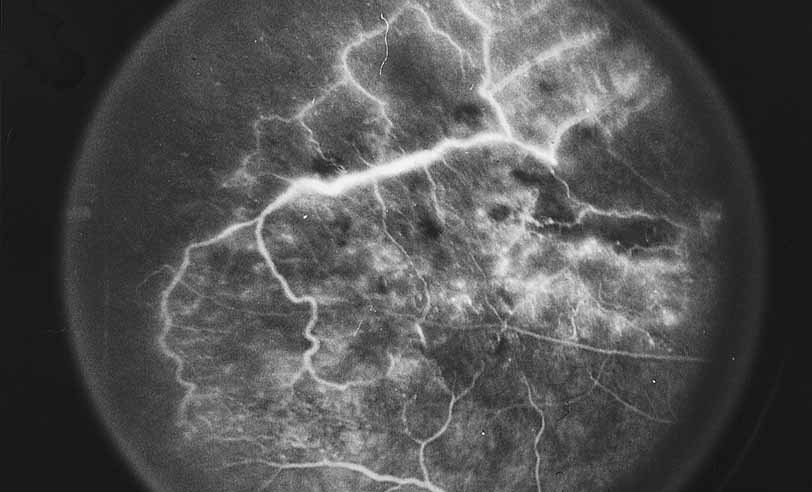

RETINAL VASCULAR INVOLVEMENT

Fluorescein angiography may be helpful in distinguishing between different forms of retinal vasculitis. Diseases such as sarcoidosis (see Figs. 14 and 15), Eales disease (see Figs. 16 and 17), pars planitis, and acute multifocal hemorrhagic retinal vasculitis (see Figs. 10, 11, 12, and 13) primarily produce inflammation of the veins (phlebitis), whereas other inflammations and infections, including acute retinal necrosis (see Figs. 19, 20, and 21),53–71 Behçet disease,46,72–74 and occasionally toxoplasmosis,1,75 preferentially involve the arterial side with secondary phlebitis not uncommon.

Fig. 19 Acute retinal necrosis. Color photograph. A young healthy man reported floaters and blurry vision. Examination revealed mild granulomatous panuveitis with disk swelling and confluent areas of peripheral retinal necrosis.

Fig. 20 Acute retinal necrosis. Fluorescein angiography shows vasculitis and patchy staining of necrotic retina.

Fig. 21 Acute retinal necrosis. Fluorescein angiography shows confluent area of necrotic retina.

One way in which angiography can be particularly helpful in cases of secondary retinal vasculitis is in evaluating the severity of inflammation initially and in response to treatment. Even occult foci of periphlebitis seen in sarcoidosis and Eale disease can be dramatically illustrated angiographically by fluorescein staining of the vessel walls in the late frames of the study (see Figs. 16 and 17).